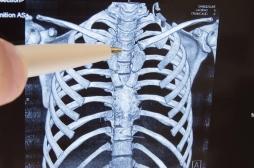

J ai Mal Bras et mains Bras et mains Tête et cou Torse et haut du dos Jambes et pied